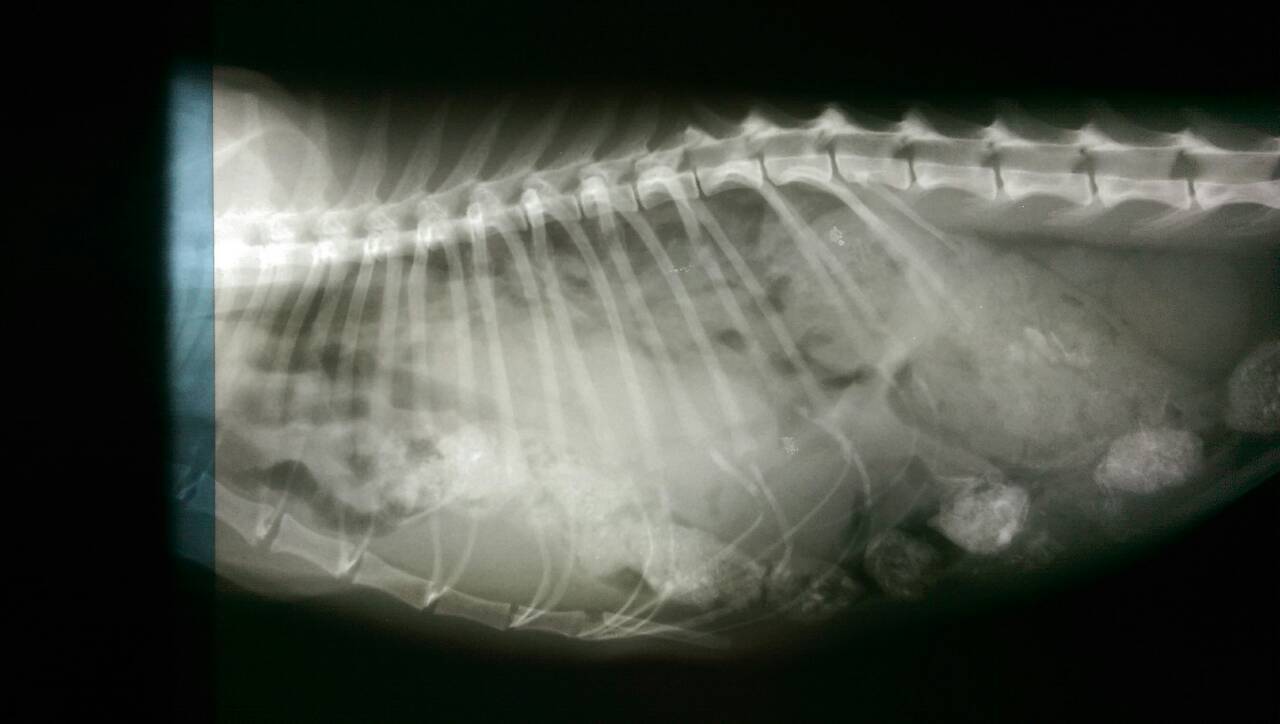

主題: 胸腔赫尼亞 申請者姓名: 陳小玲 花色: 申請日期: 2015-01-29 14:19:57 申請者部落格: 申請者臉書網址: 所在縣市/合作醫院: 嘉義市/你我牠動物醫院 治療費用: 36000元 需求人數: 39人 已結案 (2015-02-24 12:31:12) 報名人員: Portia Chen(已付款)、Ryoka Oh(已付款)、Wheat Chiang(已付款)、Ping Hussard(已付款)、Ray0322(已付款)、AmbeR Hsu(已付款)、Belinda Wang(已付款)、Chen Chris(已付款)、愛麗絲(已付款)、Bubu Wang(已付款)、Apple Chou(已付款)、Grace Lin(已付款)、mitdo43(已付款)、佩(已付款)、lavinia x3(已付款)、Josie Josie x2(已付款)、海郁(已付款)、高賽(已付款)、Tiffany Shen(已付款)、蘇小吉(已付款)、Miao Lin(已付款)、肉&菜(已付款)、dcelife(已付款)、郭瑞希、毛絨絨(已付款)、戴戴(已付款)、Cathy(已付款)、zoelo(已付款)、綺(已付款)、Yen-Yuan Wang(已付款)、May Chuang(已付款)、Candace Shiue x2(已付款)、Lewis Wong x3(已付款)、Misu Sweet(已付款)、 候補人員: 動物病情說明: 橘橘是我餵養二年半的貓,一直在我的餵養區生活,最近發現牠一直喘氣,每次吃食物時總是呼吸急促,造成腹部快速收縮,因為這二星期天氣很冷,我以為牠感冒了,包了二次藥回來投藥,1/6一次,1/14一次,但好像沒改善,沒想到今天看到牠竟然一直喘,我回家拿了提籠和誘捕籠,先放了提籠後,牠竟然乖乖的走進提籠了,我想牠一定生病了,趕緊送去醫院。

醫生說牠的呼吸不正常,應該被撞到了,而且有一段時間了,要照X光看看,結果一照完竟然是,肝,腸跑到胸腔去了,才會造成呼吸窘迫,難怪牠每次吃飯都一邊吃一邊呼吸困難,所以要趕緊開刀,我擔心牠的肝腸不知道會不會壞死,希望能趕快得到協會的幫助。動物近況說明: 1/21抓到橘橘,檢查出來是胸腔赫尼亞,1/22馬上開刀,因為整個腹腔的器官都擠到胸腔去了。